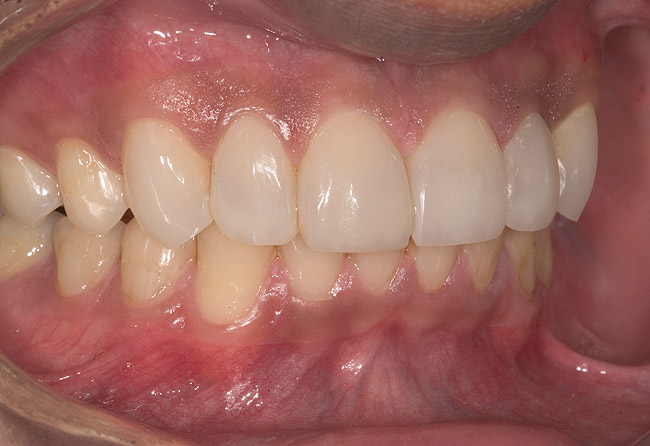

Figure 15  Maximum intercuspation (MIP) after restoration of the lost palatal anatomy.

Figure 15

Figure 16  1:2 right lateral view; posteriors discluded in MIP.

Figure 16

Figure 17  1:2 left lateral view; posteriors discluded in MIP.

Figure 17